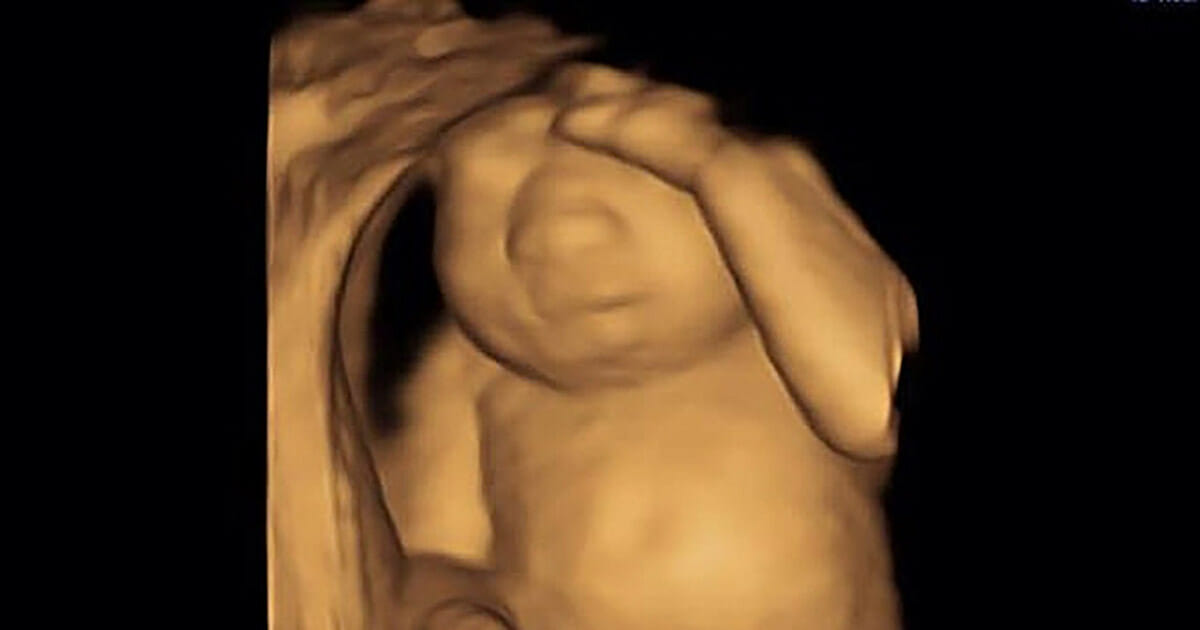

Eva växte i livmodern, men hon hade ingen hjärna. Och det skulle inte dröja efter förlossningen innan hon blev en ängel.

Jag såg på henne medan hon låg där, hennes stora mage med vår dotter som sparkade, en dotter som inte kommer att leva i mer än några dagar och det blev så överväldigande hur otrolig den här kvinnan är. Jag är författare så när jag känner något brukar jag skriva ner det.

Hennes rygg värker. Hennes fötter är ömma. Hon genomlever allt det roliga som en graviditet medför. Men ljuset vid slutet av hennes nio månader långa tunnel kommer att bli till ett mörker hon aldrig känt innan, bara ett par timmar eller dagar efter att Eva är född.